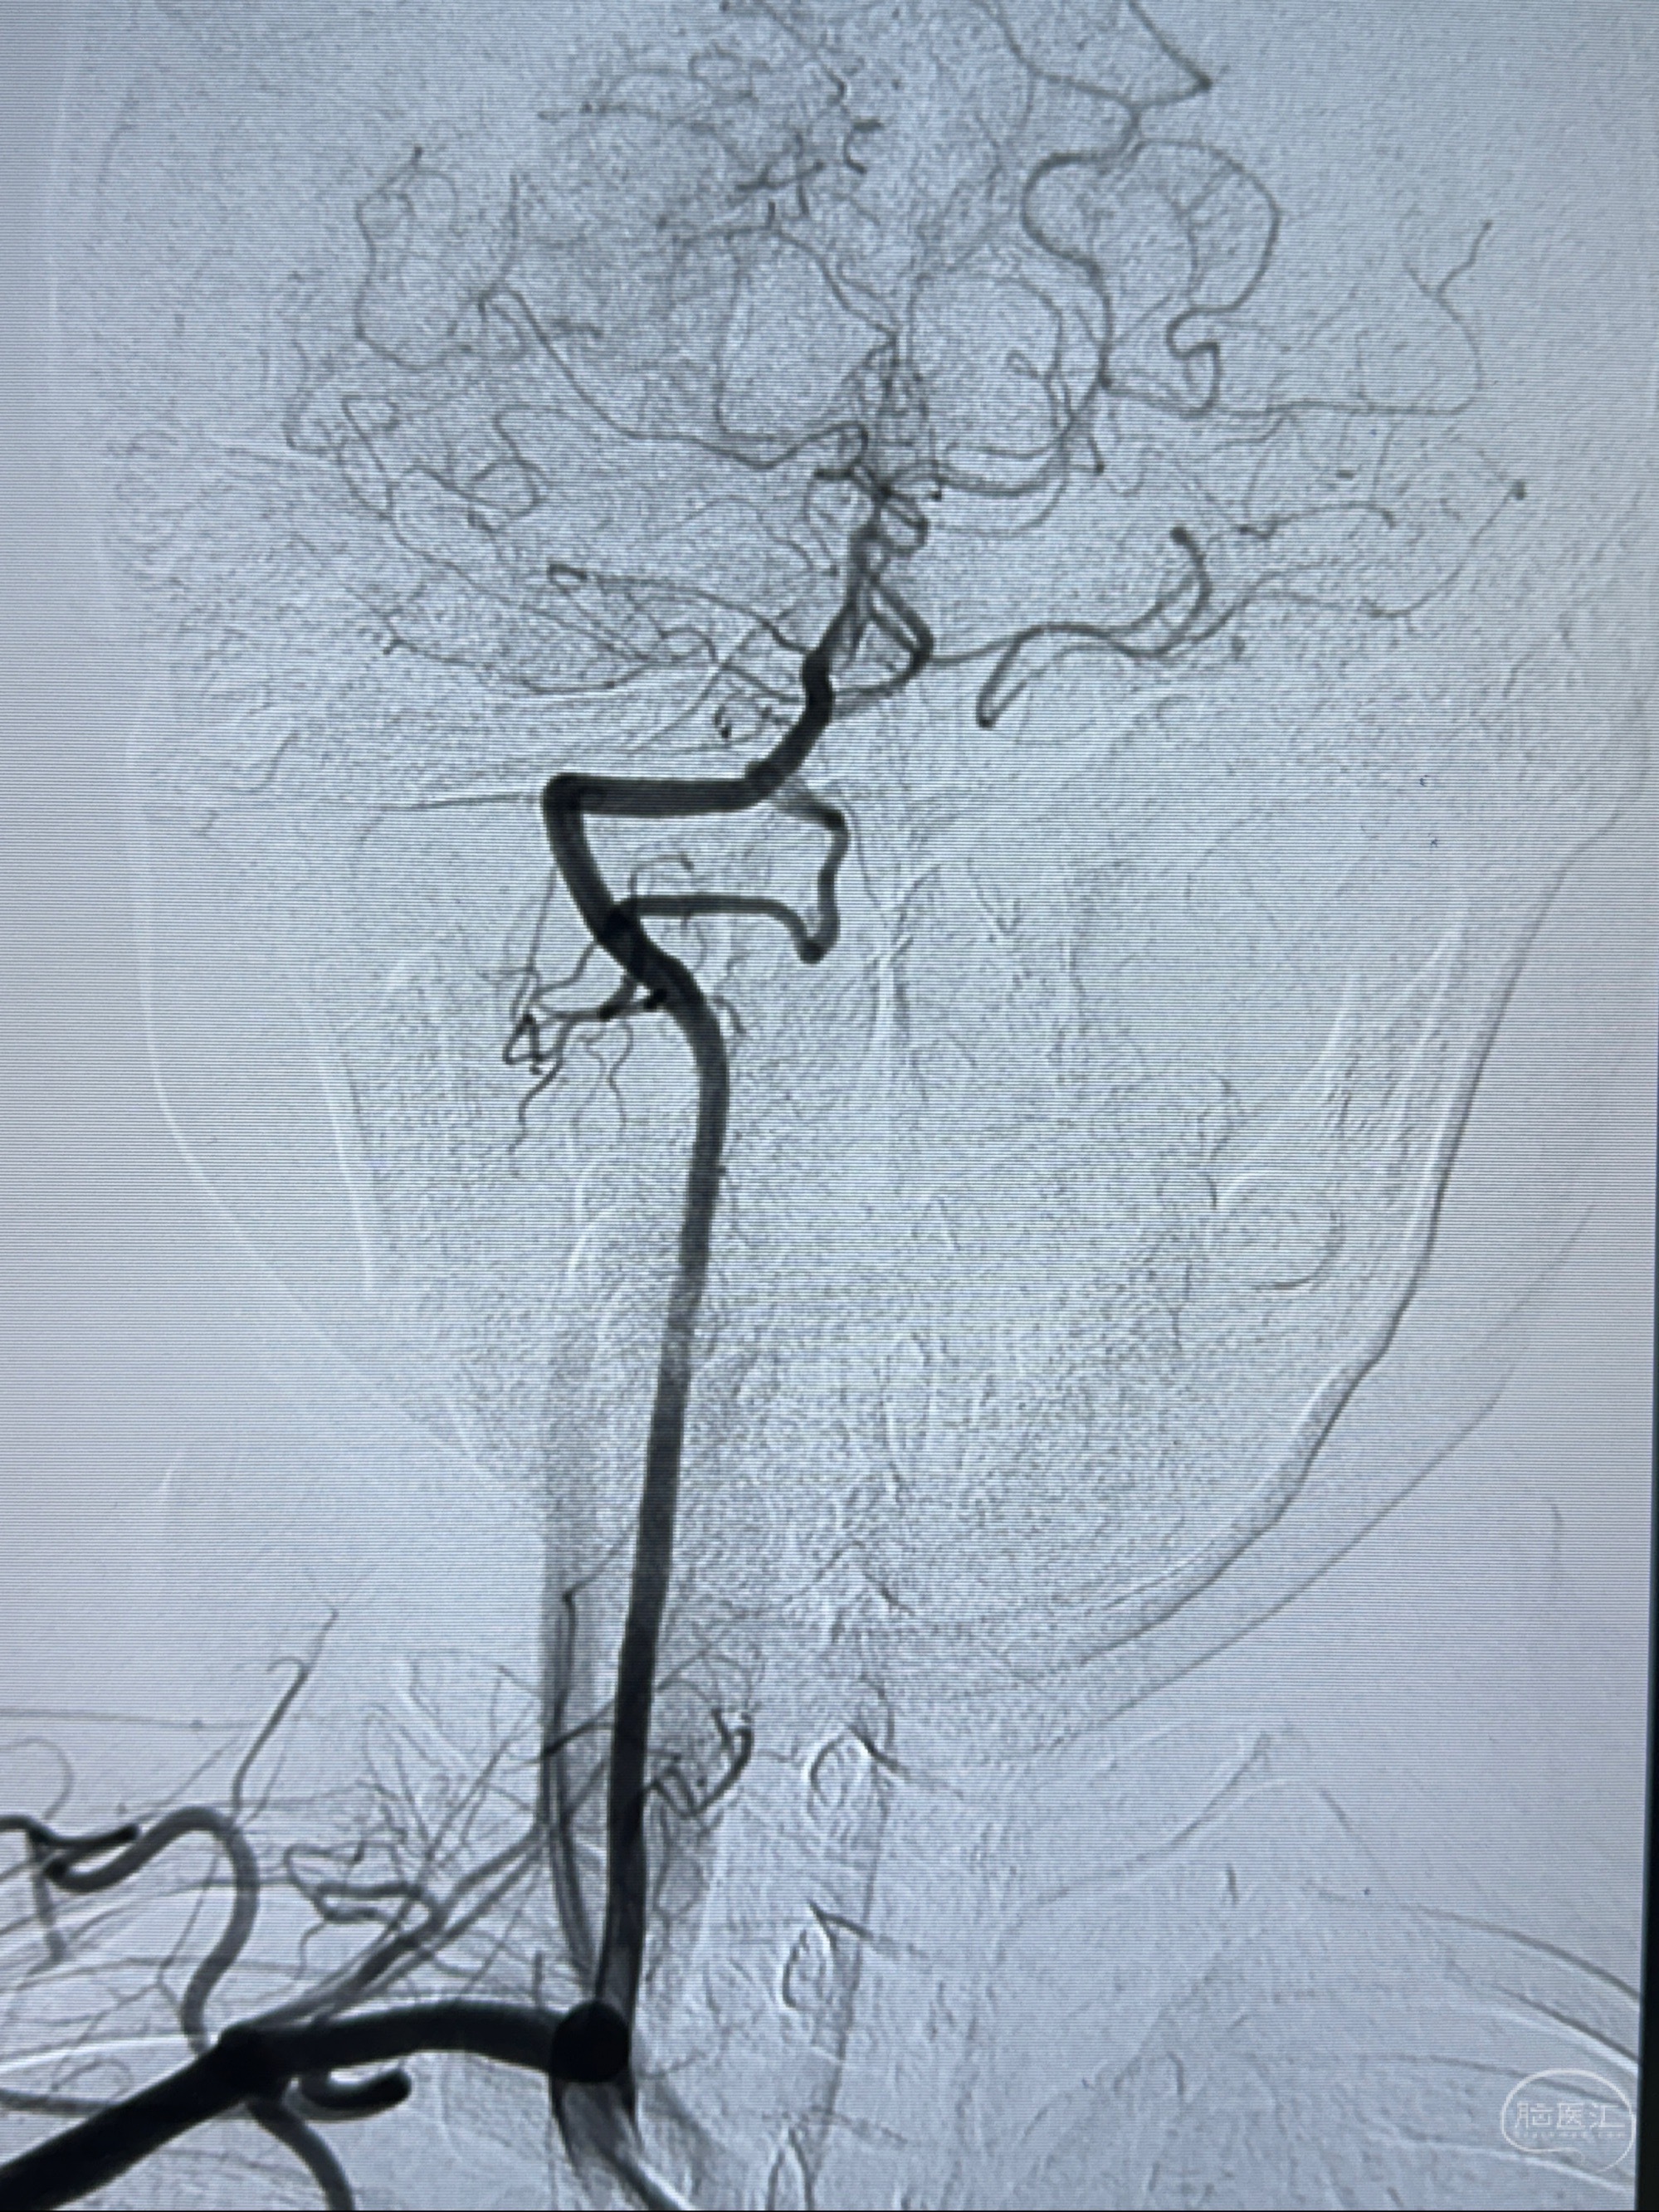

2023-11-13DSA:左侧颈内动脉眼动脉后壁动脉瘤

2023-11-29全麻下行NeuroformEZ4.5-20mm支架辅助栓塞